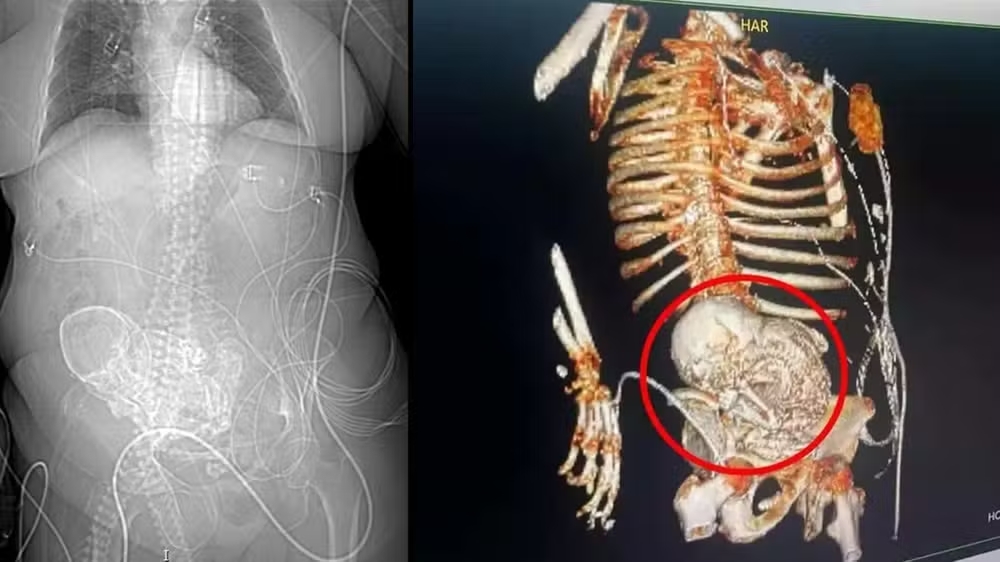

Bizarro

Há 2 anos

Médica causa espanto ao detalhar caso bizarro de paciente

O vídeo, que já viralizou no X, antigo Twitter, atingiu milhões de visualizações